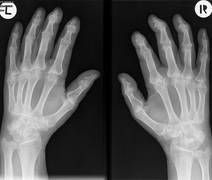

Rheuma beschreibt den Sammelbegriff für viele unterschiedliche Erkrankungen: Experten sprechen von über 400 verschiedenen Rheumaerkrankungen, wie Arthritis Urica, Arthrose, chronische Polyarthritis, Morbus Bechterew, Perichondritis, das Fibromyalgie-Syndrom, u.v.m. Rund zwei Millionen Österreicherinnen und Österreicher leben mit Rheuma, darunter auch 1000 Kinder unter 16 Jahren.